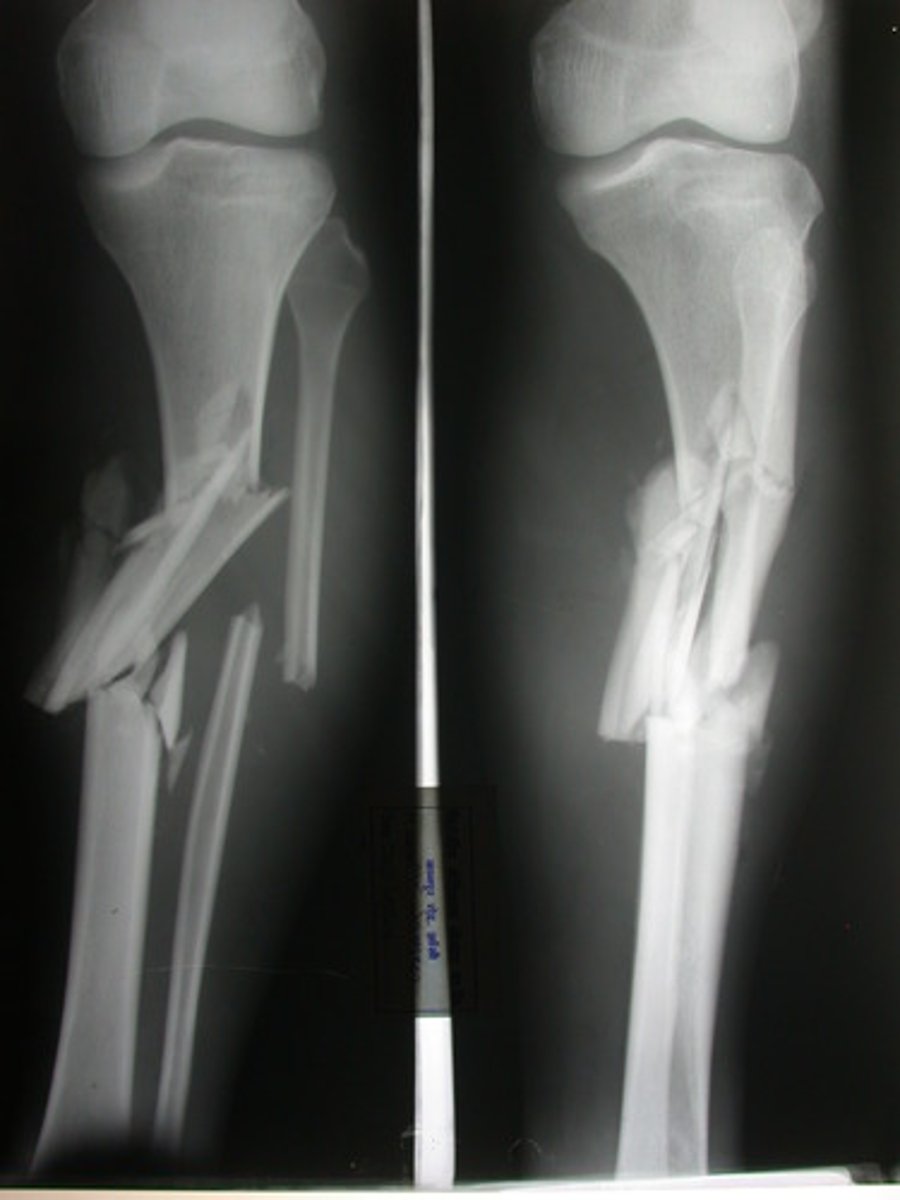

Comminuted fracture

fracture in which the bone is splintered or crushed